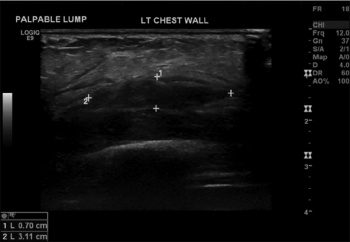

Figure 2: CT thorax – low attenuating lesion in overlying anterior ribs/costochondral areas 5 to 7 with associated intercostal muscle thickening

Figure 2: CT thorax – low attenuating lesion in overlying anterior ribs/costochondral areas 5 to 7 with associated intercostal muscle thickening(click to enlarge)

A CT evaluation showed a low attenuating lesion overlying the anterior fifth-seventh ribs associated with intercostal muscle thickening (Figure 2), which may represent resolving haematoma or abscess formation.